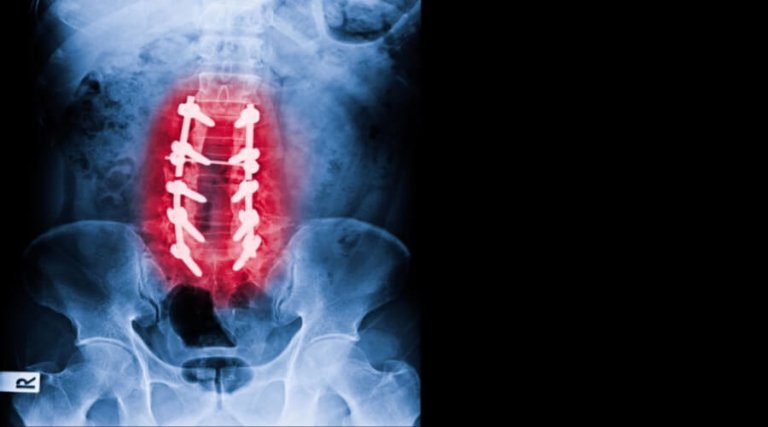

تُعد عملية تثبيت الفقرات من الجراحات الدقيقة التي تُجرى لعلاج العديد من مشكلات العمود الفقري، مثل التزحزح الفقري، والانزلاق الغضروفي المنفجر، وكسور الفقرات، وعدم إتزان العمود الفقري. وتهدف هذه الجراحة إلى إعادة تثبيت الفقرات المصابة وتقليل الضغط على الأعصاب والحبل الشوكي، مما يساهم في تخفيف الألم واستعادة القدرة على الحركة بصورة أفضل.